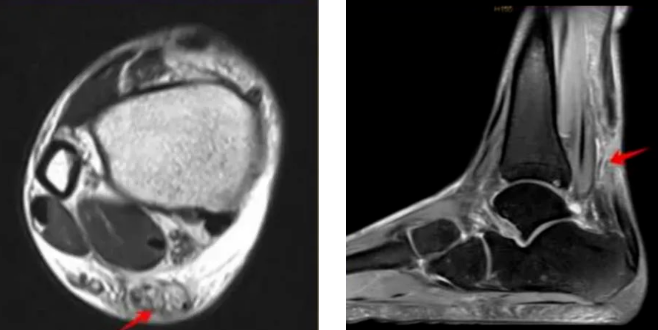

就醫(yī)后,最常用明確診斷的影像學(xué)檢查主要包括超聲檢查和MRI檢查,對懷疑有跟腱止點撕脫骨折者,還需要完善X線、CT檢查。